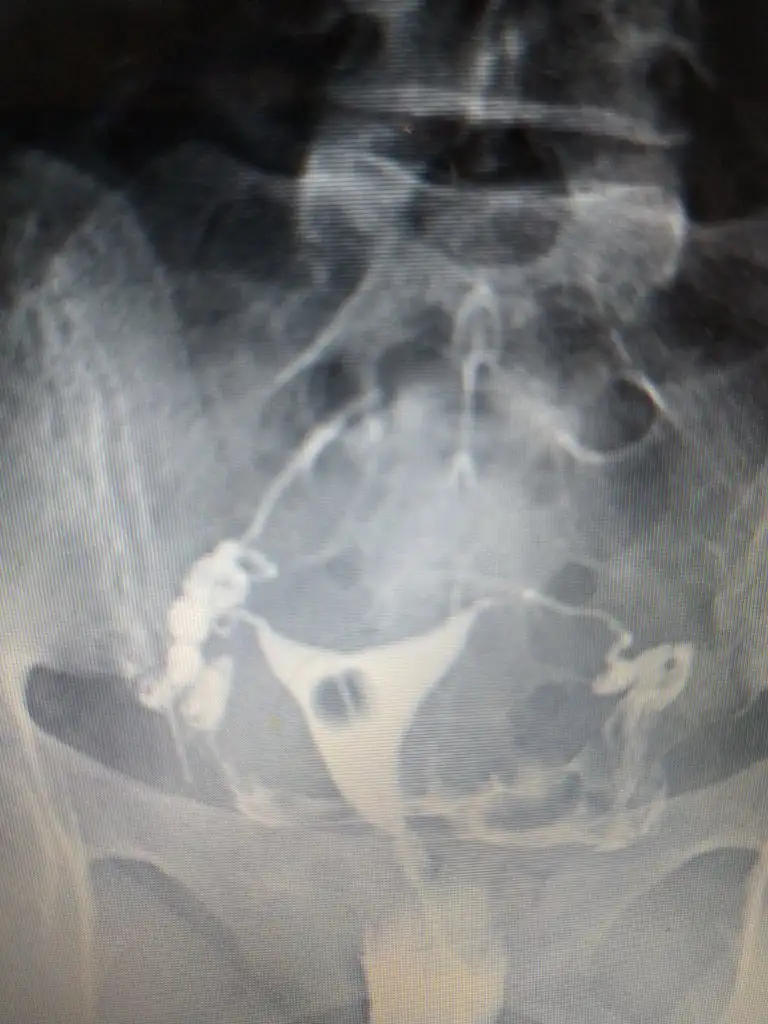

Onun hatlar karışık biraz. Çekim sonrası radyologun mesai saati bittiği için rapor yetişmemiş. Pazartesi alacak sonucunu. Kendi doktoru tüplerden birinde tıkanıklık var gibi konuşmuş ama başka doktorlara da göstermiş, basınçla açılmış demişler